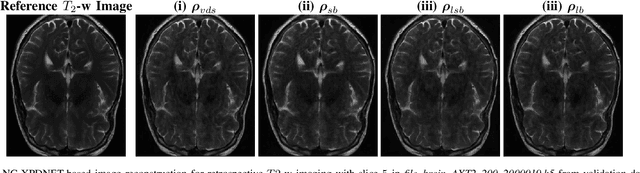

Abstract:We perform a qualitative analysis of performance of XPDNet, a state-of-the-art deep learning approach for MRI reconstruction, compared to GRAPPA, a classical approach. We do this in multiple settings, in particular testing the robustness of the XPDNet to unseen settings, and show that the XPDNet can to some degree generalize well.

Abstract:The SPARKLING algorithm was originally developed for accelerated 2D magnetic resonance imaging (MRI) in the compressed sensing (CS) context. It yields non-Cartesian sampling trajectories that jointly fulfill a target sampling density while each individual trajectory complies with MR hardware constraints. However, the two main limitations of SPARKLING are first that the optimal target sampling density is unknown and thus a user-defined parameter and second that this sampling pattern generation remains disconnected from MR image reconstruction thus from the optimization of image quality. Recently, datadriven learning schemes such as LOUPE have been proposed to learn a discrete sampling pattern, by jointly optimizing the whole pipeline from data acquisition to image reconstruction. In this work, we merge these methods with a state-of-the-art deep neural network for image reconstruction, called XPDNET, to learn the optimal target sampling density. Next, this density is used as input parameter to SPARKLING to obtain 20x accelerated non-Cartesian trajectories. These trajectories are tested on retrospective compressed sensing (CS) studies and show superior performance in terms of image quality with both deep learning (DL) and conventional CS reconstruction schemes.

Abstract:We present a modular cross-domain neural network the XPDNet and its application to the MRI reconstruction task. This approach consists in unrolling the PDHG algorithm as well as learning the acceleration scheme between steps. We also adopt state-of-the-art techniques specific to Deep Learning for MRI reconstruction. At the time of writing, this approach is the best performer in PSNR on the fastMRI leaderboards for both knee and brain at acceleration factor 4.